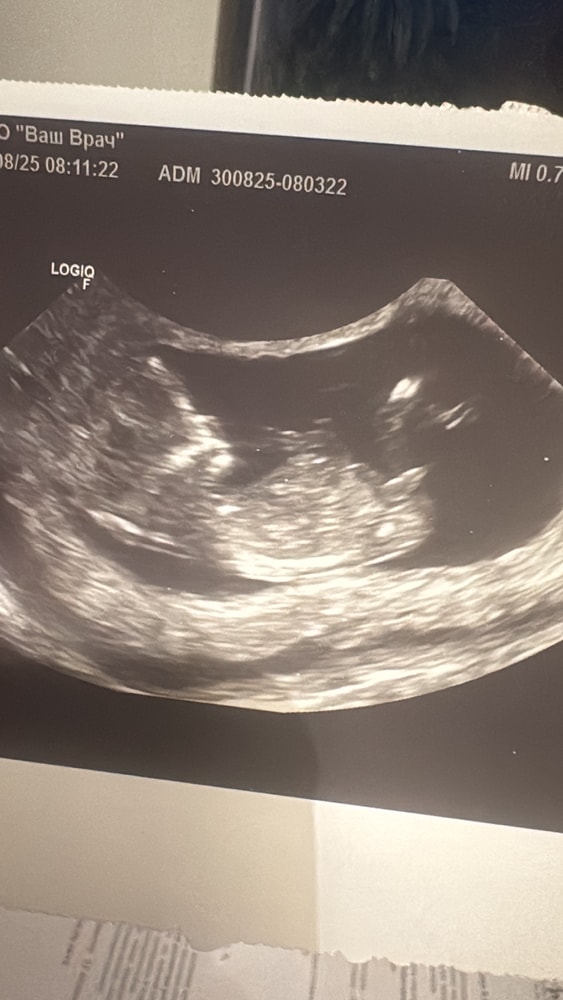

Кто разбирается. Подскажите , можно ли узнать пол по этому фото узи. Срок на нем 12 недель.

Мальчик)